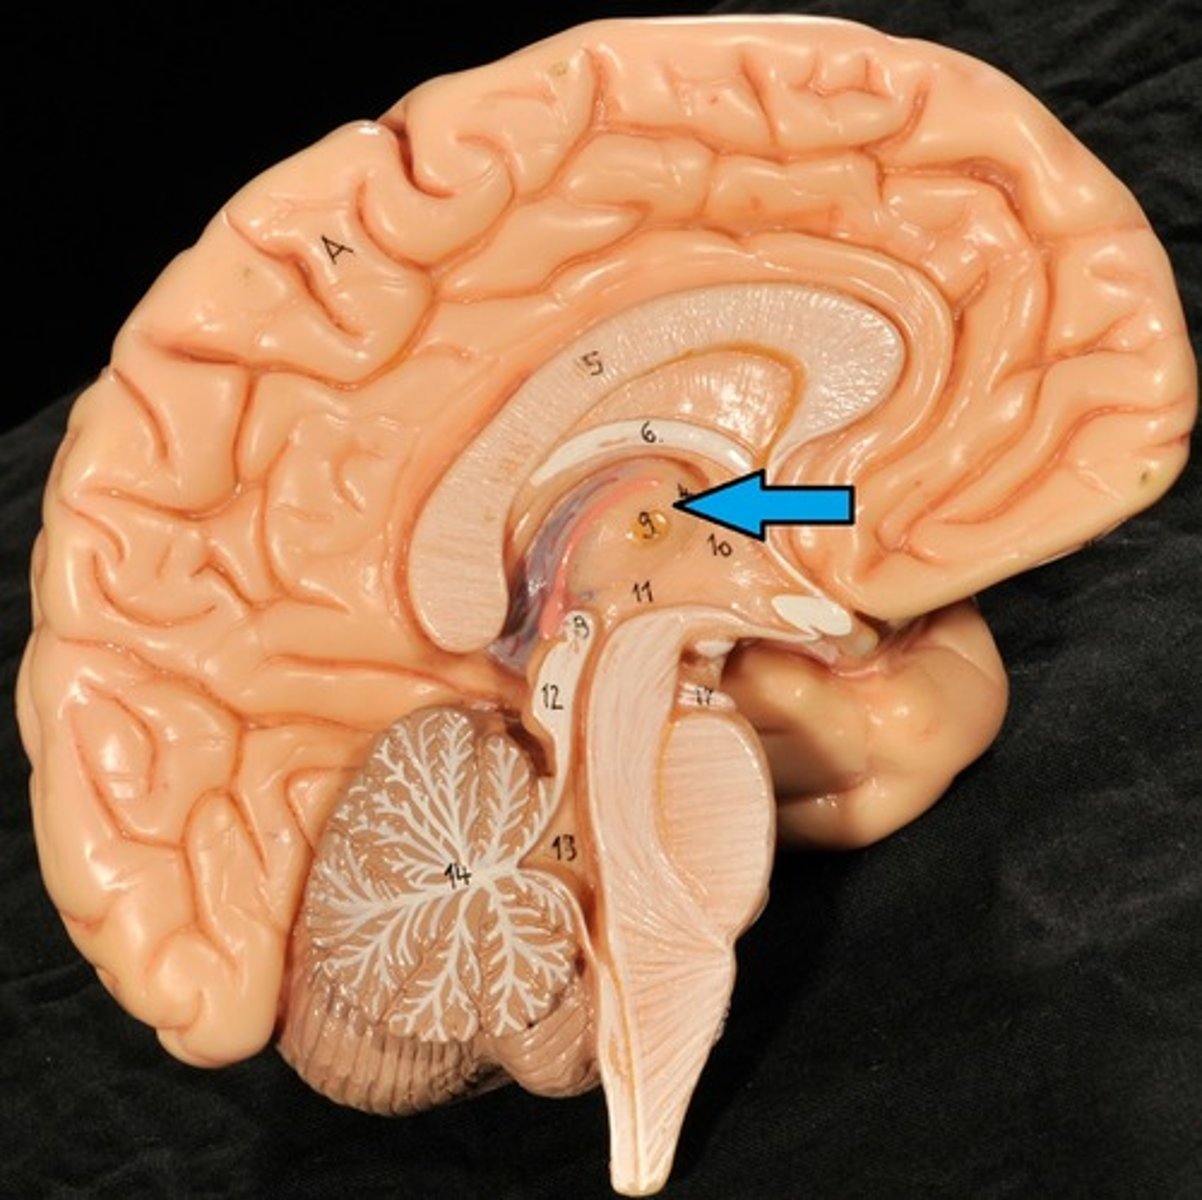

Diencephalon

Sits on top of the brain stem,

Enclosed by the cerebral hemispheres,

Made up of 3 parts: the Thalamus, Hypothalamus, and Epithalamus

Thalamus

Bilateral egg-shaped nuclei, which forms superolateral walls 3rd ventricle,

Relay station for information coming into cerebral cortex:

-Will sort and edit the info

-Also provides a crude recognition of sensation as pleasant or unpleasant before it sends info on to cortex where specific stimulus localization and discrimination still occur

Hypothalamus

Located under thalamus where it caps the brain stem and forms inferolateral walls of 3rd ventricle,

Main visceral (involuntary) control center of body is vitally important to overall body homeostasis (few tissues in body escape its influence),

Epithalamus

Forms the roof of the 3rd ventricle,

Houses the pineal gland or body (an endocrine gland) (Melatonin production: sleep/wake cycle),

Includes the choroid plexus (forms cerebrospinal fluid- CSF)